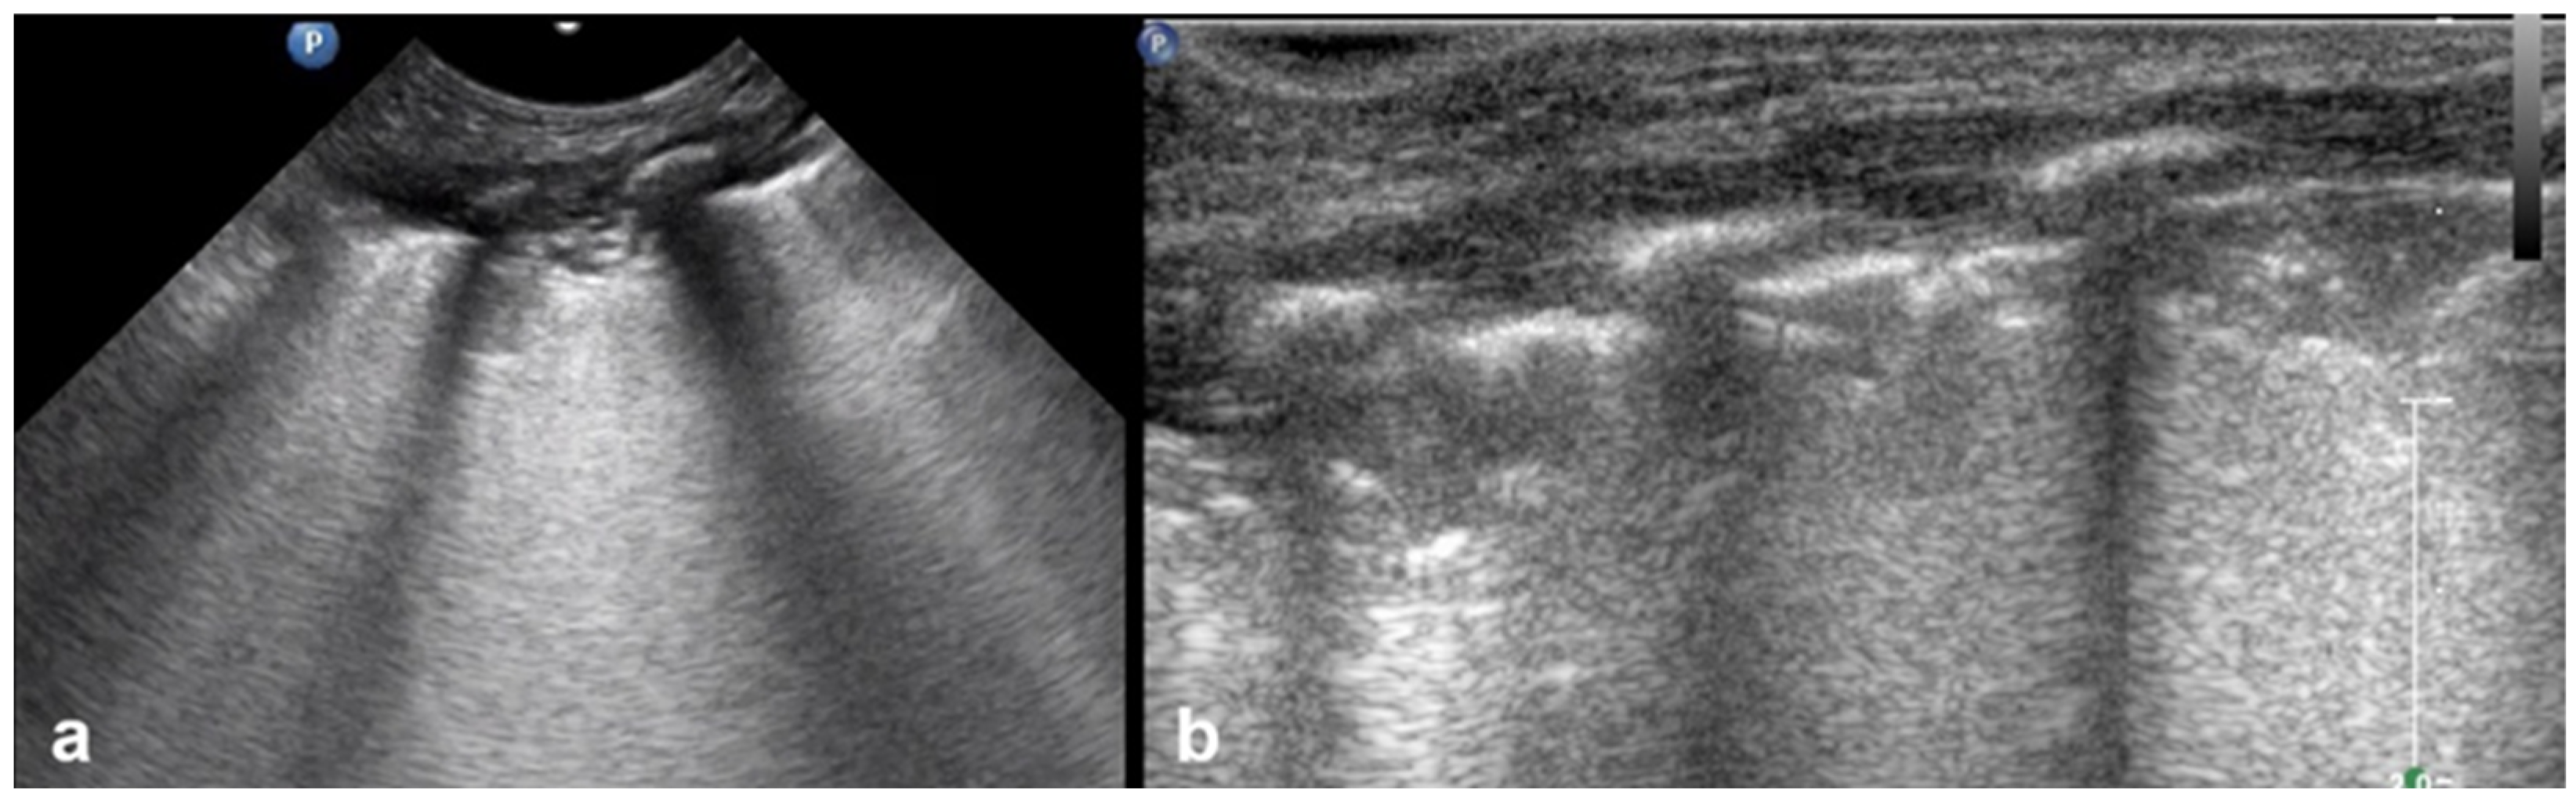

3.1.6. Sinusoid Sign

In cases of pleural effusion, the accumulation of fluid between the pleural layers causes separation of the visceral and parietal pleura. LUS assessment of this condition in M-mode is associated with the presence of a characteristic sinusoidal pattern, resulting from the cyclical movement of the lung line toward the pleural line during inhalation and away from the pleural line during exhalation. The presence of this “sinusoid sign” indicates the presence of low-viscosity fluid within the pleural space, separating the visceral and parietal pleura. This finding can assist in differentiating pleural effusion from pleural thickening, as its presence is indicative of mobile, free-flowing fluid typically associated with pleural effusions (Figure 7) [17].

Figure 7.

Sinusoid sign: (a) CXR: left-sided consolidation (is there any pleural effusion?). (b) LUS reveals fluid, a finding based on the sinusoid sign, with a characteristic sinusoidal pattern due to the cyclical movement of the lung line toward the pleural line during inhalation and away from the pleural line during exhalation (L: lung; SPL: spleen).